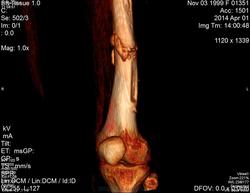

Молодая дама (14 лет) с переломом срдней трети диафиза левого бедра в анамнезе (декабрь 2012 г). Ломала ногу несколько раз в этом месте. Сейчас состояние после МОС. Как следует понимать изменения в кости, формируется ли ложный сустав?

Похоже ложный сустав сформировался. Но при нём обычно большие напластования костной мозоли, здесь их нет. В таких случаях смотрю при скопии подвижность.

Ох, не хочется думать о ложном суставе в 14 лет... По срокам под ложный сустав подходит, он характеризуется замыканием костномозгового канала с формированием подобий суставных поверхностей. У нее же есть хиленькая периостальная костная мозоль по задней поверхности бедра удерживающая отломки в правильном положении. Я склонна думать, что это скорее застарелый перелом (оно же замедленная консолидация). Здесь очень важно посмотреть предыдущие снимки (поиск рефрактуры, либо отсутствия полной консолидации).

При выраженной костной мозоли между отломками ложный сустав формироваться не может в принципе.

Настоящего, родного ложного сустава пока нет, хотя костномозговой канал дистального отломка уже закрыт - образовалась склерозированная замыкательная пластина. Варусная деформация почти в 165 градусов... Я бы заключилась неполной консолидацией и варусной деформацией, прогностически формирование ложного сустава очень вероятно.